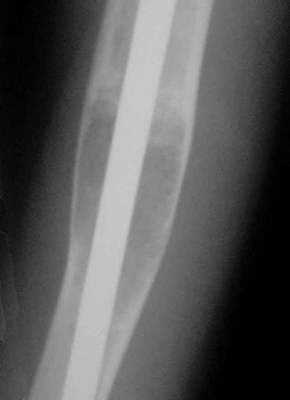

Im September 2000 - zwei Jahre später - hatte die Cyste an Größe zugenommen. Erhöhte Frakturgefahr bestand. Für das Ausräumen der Cyste war der Defekt zu groß und das Auffüllen mit Fremdspongiosa zu risikoreich.

Es wurde nun nichts anderes gemacht, als der Markraum aufgebohrt und ein "Seidel"-Nagel eingebracht und distal gespreizt. Wichtig hierbei ist, den Nagel soweit einzubringen, dass dieser nicht über den Oberarmkopf hinausragt und die Schulterbewegung nicht beeinträchtigt wird. Ein proximalVerriegelung ist nicht erforderlich.